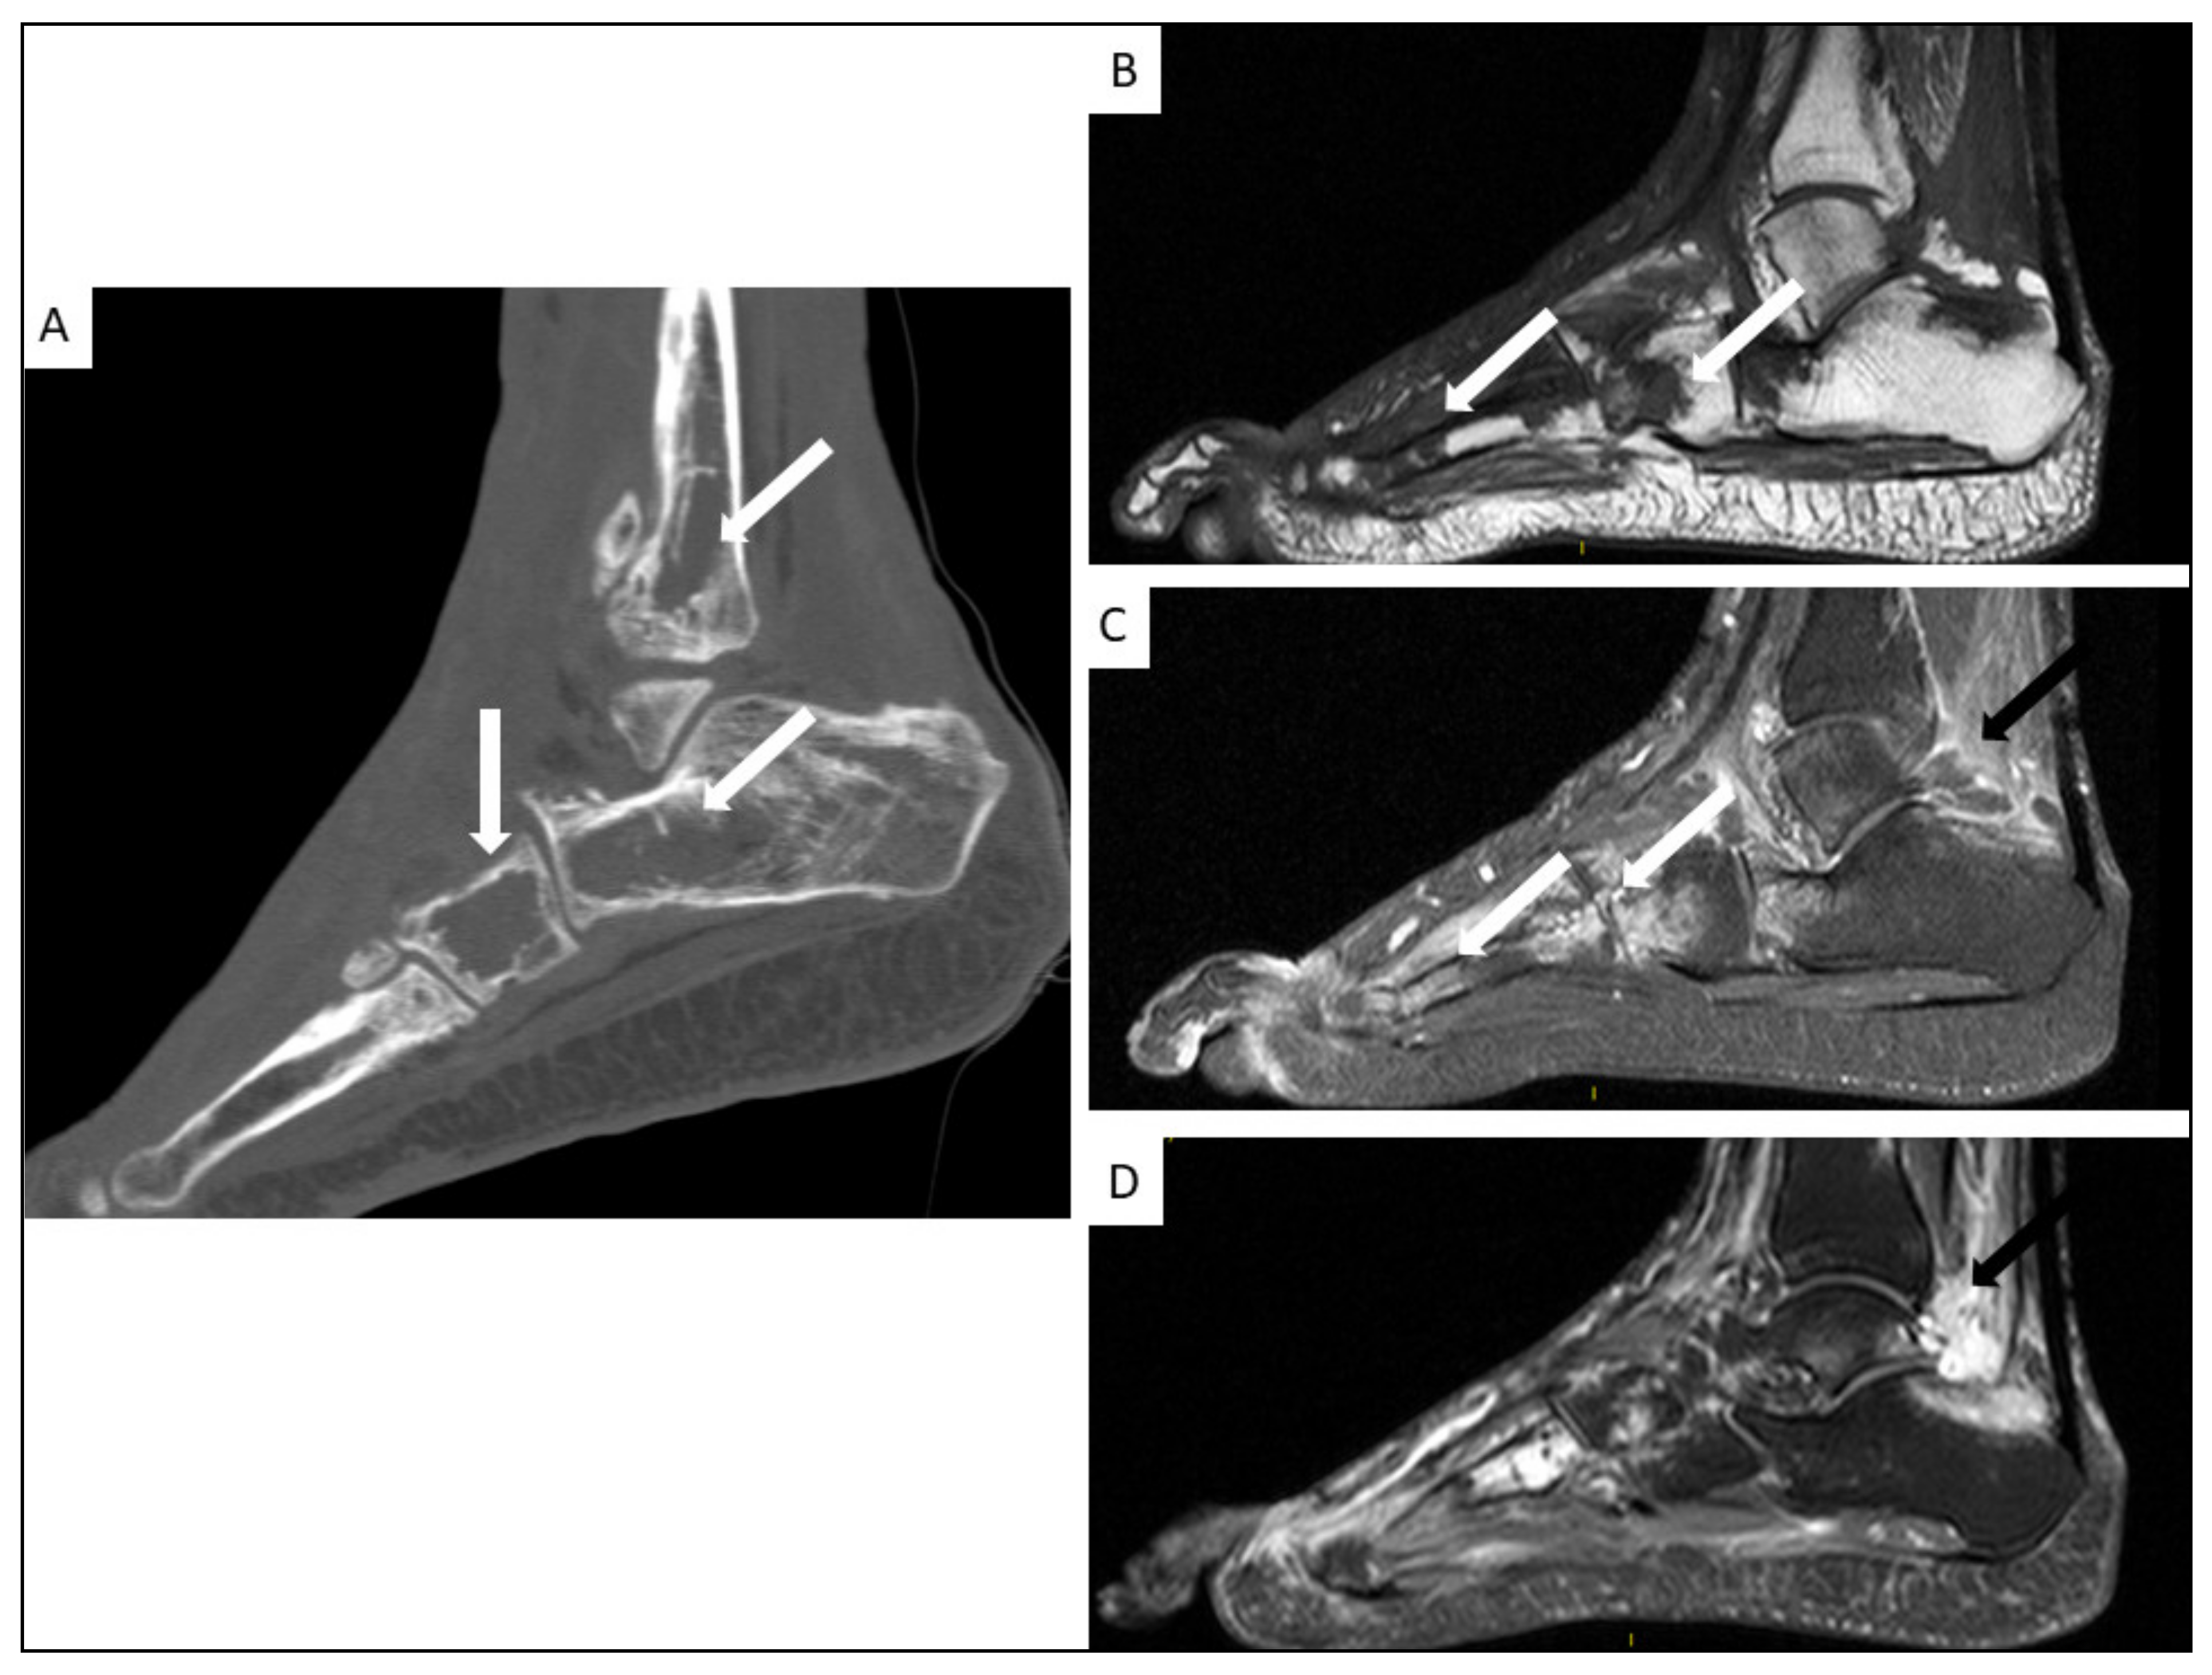

5.4. Musculo-Skeletal KS

- Restrepo, C.S.; Martínez, S.; Lemos, J.A.; Carrillo, J.A.; Lemos, D.F.; Ojeda, P.; Koshy, P. Imaging Manifestations of Kaposi Sarcoma. Radiographics 2006, 26, 1169–1185. [Google Scholar] [CrossRef]

- Caponetti, G.; Dezube, B.J.; Restrepo, C.S.; Pantanowitz, L. Kaposi Sarcoma of the Musculoskeletal System: A Review of 66 Patients. Cancer 2007, 109, 1040–1052. [Google Scholar] [CrossRef]